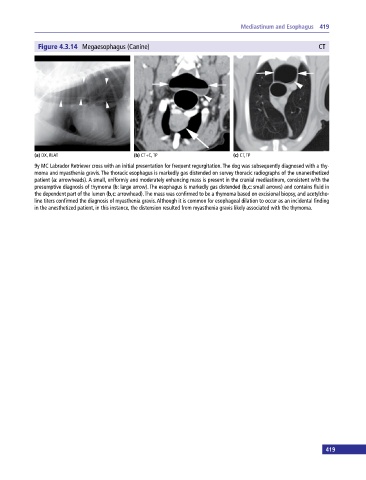

Figure 4.3.14 Megaesophagus (Canine) CT

(a) DX, RLAT (b) CT+C, TP (c) CT, TP

9y MC Labrador Retriever cross with an initial presentation for frequent regurgitation. The dog was subsequently diagnosed with a thy

moma and myasthenia gravis. The thoracic esophagus is markedly gas distended on survey thoracic radiographs of the unanesthetized

patient (a: arrowheads). A small, uniformly and moderately enhancing mass is present in the cranial mediastinum, consistent with the

presumptive diagnosis of thymoma (b: large arrow). The esophagus is markedly gas distended (b,c: small arrows) and contains fluid in

the dependent part of the lumen (b,c: arrowhead). The mass was confirmed to be a thymoma based on excisional biopsy, and acetylcho

line titers confirmed the diagnosis of myasthenia gravis. Although it is common for esophageal dilation to occur as an incidental finding

in the anesthetized patient, in this instance, the distension resulted from myasthenia gravis likely associated with the thymoma.